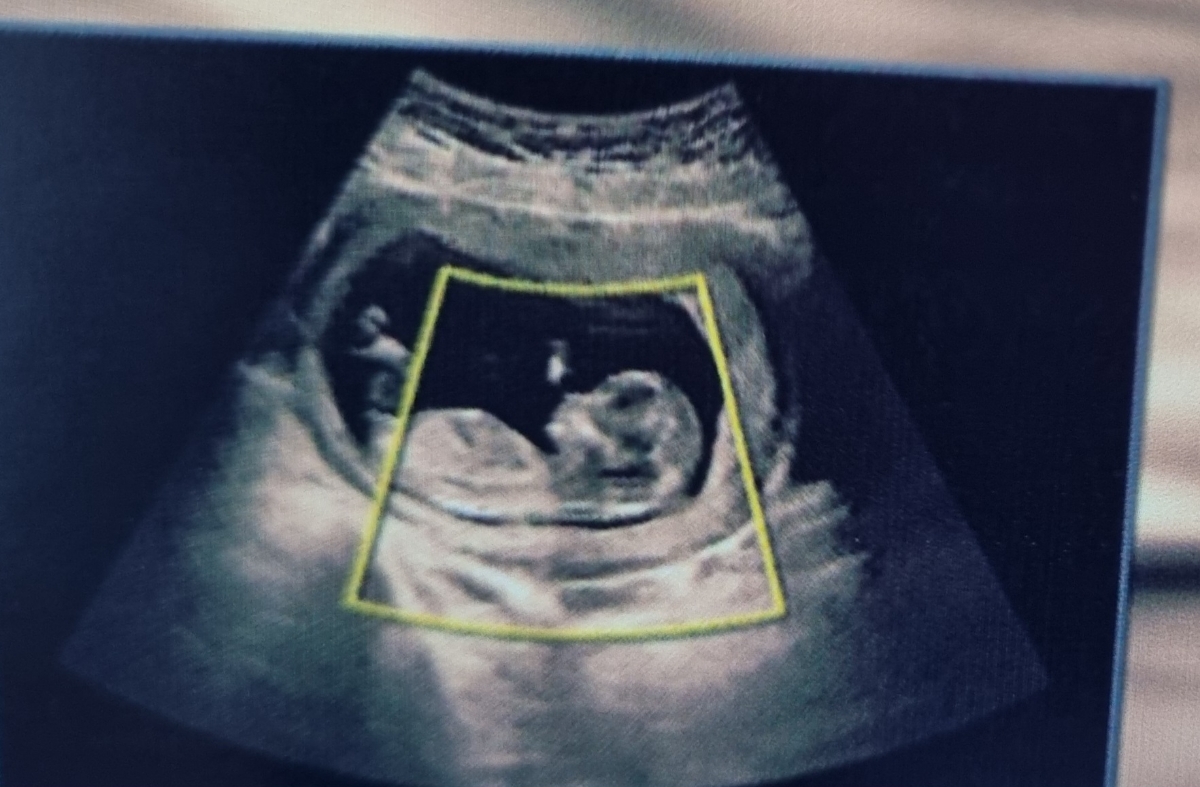

دل انگیز .

ای خدا گوگولی

خداحفظش کنه .به احتمال ۹۹درصد میگم دختره😍😍😍😍😍

عکس سونوت خیلی شبیه عکس سونوی دخترام هست

گردی سر و پیشونی

گردی سرش

سرش عزیزم

پیشونی تاپشت گردن

گرد هست

چه عکس خوبی دکتر با سلیقه بوده همیشه همینجا برو🤣

بنظر منم دختره کله اش گرد و ظریف به نظر میرسه